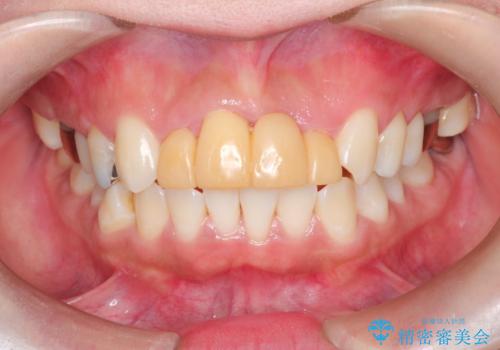

3年間仮歯 前歯セラミックブリッジ

- 3年間仮歯のまま過ごしていたそうです。 色の変色と臭いが気になり来院されました。

仮歯に変えた時点で臭いや色などが改善され、気に入っていただけました。